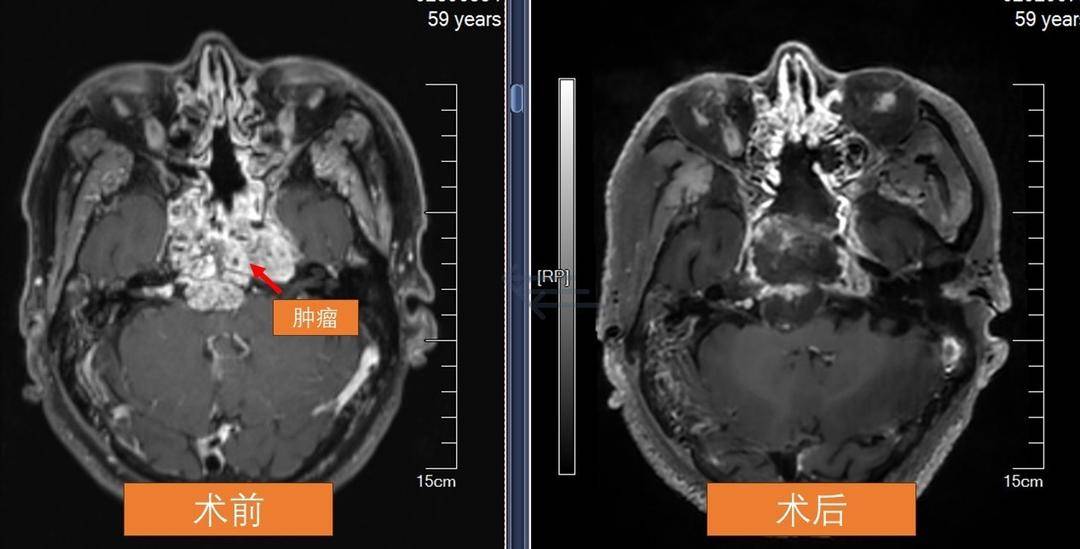

“医生,我这头疼得要炸了,吃止痛药都没用了……”前不久,在苏州大学附属第一医院神经外科门诊,从泰州赶来的李先生满脸疲惫,他已经一连多天头痛难忍,彻夜难眠。几年前他曾因颅底脊索瘤接受过手术,如今肿瘤复发,疼痛反复加重,止痛药也无法缓解。经检查,肿瘤直径已达5厘米,压迫脑干,紧紧缠绕唯一通畅的颈内动脉,而另一侧血管早已闭塞。情况严重,甚至威胁生命。苏大附一院神经外科团队以鼻腔为通道进行手术,在毫米级的空间中精准操作,将肿瘤分块切除,完成“颅内拆弹”。

来到苏大附一院检查后,结果让人不寒而栗——几年前曾做过手术的颅底脊索瘤再次复发。李先生其实早知道自己体内藏着这个“老对手”,只是没想到它会卷土重来得这么快、这么狠。此时,肿瘤已长到直径约5厘米,压迫脑干,还缠绕着唯一通畅的左侧颈内动脉。右侧血管早已闭塞,这一根“独苗”,成了维系他生命的最后通路。

术后,李先生的头痛消失了,视力慢慢恢复,整个人精神了许多。医生复查时发现,肿瘤被最大程度切除后,颅底愈合良好,关键的血管也安然无恙。